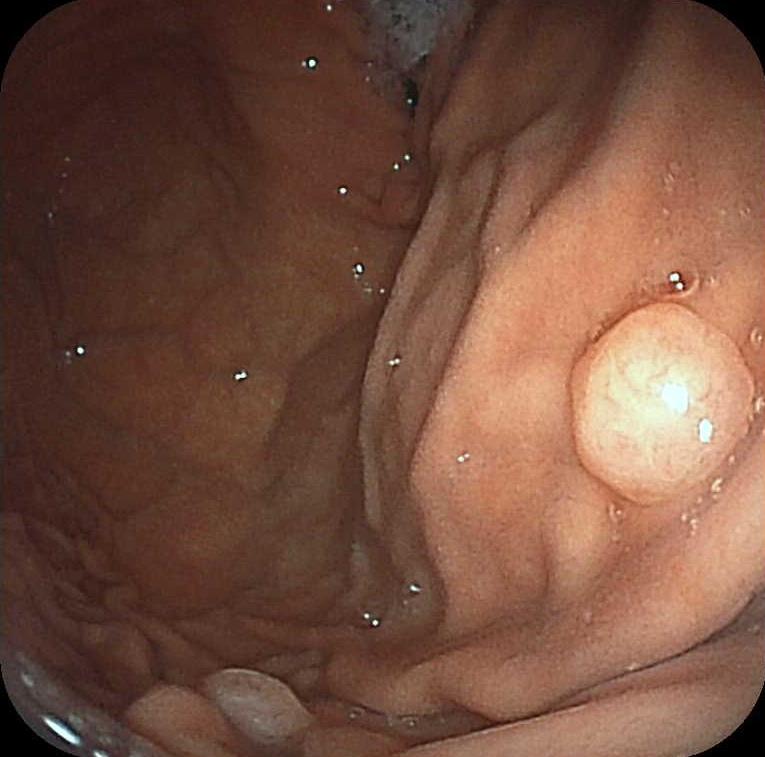

胃ポリープ

胃の内腔に粘膜の一部が隆起したものを胃ポリープといいます。

胃ポリープは過形成性ポリープ、胃底腺ポリープ、特殊型(炎症性など)に分けられます。

ほとんどは胃底腺ポリープ、過形成性ポリープで特殊型は見られることはほとんどありません。

胃底腺ポリープは癌化することはなく、経過観察で良いといわれております。

過形成性ポリープは大きくなると癌化することがあります。また、過形成性ポリープができる胃は癌が発生する可能性のある状態でもあります。内視鏡でのフォローが必要です。

胃癌検診でポリープは見られるが、精密検査不要といわれることがあります。胃底腺ポリープだと判断しているためです。しかし、厳密に言うと、100パーセント胃底腺ポリープだと言い切ることはできないと思います。内視鏡で見る必要があります。

写真は胃底腺ポリープです。